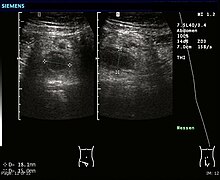

Abdominal ultrasonography, preferably with doppler sonography, is useful to detect appendicitis, especially in children. Ultrasound can show the free fluid collection in the right iliac fossa, along with a visible appendix with increased blood flow when using color Doppler, and noncompressibility of the appendix, as it is essentially walled-off abscess. Other secondary sonographic signs of acute appendicitis include the presence of echogenic mesenteric fat surrounding the appendix and the acoustic shadowing of an appendicolith.[45] In some cases (approximately 5%),[46] ultrasonography of the iliac fossa does not reveal any abnormalities despite the presence of appendicitis. This false-negative finding is especially true of early appendicitis before the appendix has become significantly distended. Also, false-negative findings are more common in adults where larger amounts of fat and bowel gas make visualizing the appendix technically difficult. Despite these limitations, sonographic imaging with experienced hands can often distinguish between appendicitis and other diseases with similar symptoms. Some of these conditions include inflammation of lymph nodes near the appendix or pain originating from other pelvic organs such as the ovaries or Fallopian tubes. Ultrasounds may be either done by the radiology department or by the emergency physician.[47]

Ultrasound showing appendicitis and an appendicolith[48]